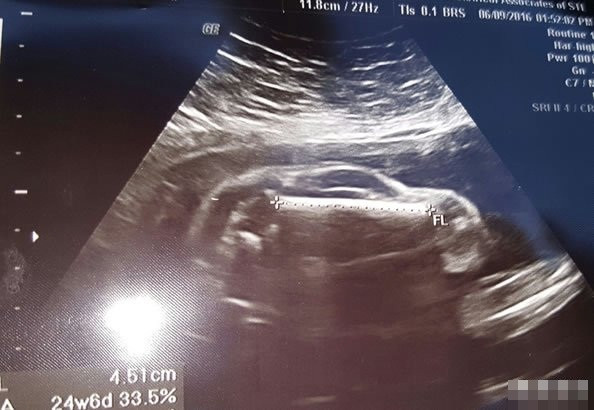

Mới đây, một cư dân mạng đã chia sẻ bức ảnh siêu âm kỳ lạ trước khi sinh của vợ mình, khiến nhiều người ngạc nhiên thích thú.

Trong bức ảnh siêu âm của người vợ, có thể thấy rõ ràng cô đang mang thai một em bé kháu khỉnh. Thế nhưng kỳ lạ thay, càng nhìn, em bé càng giống như một chiếc xe hơi thể thao, khiến người cha tương lai vô cùng hào hứng.

Tất cả mọi người đều đồng ý rằng, trong bức ảnh siêu âm này, hình dáng của thai nhi trông giống như một chiếc xe hơi thể thao. Thậm chí hình ảnh còn rất giống các bộ phận bánh xe phía trước và phía sau, cửa kính, phần mui, phần thân sau.